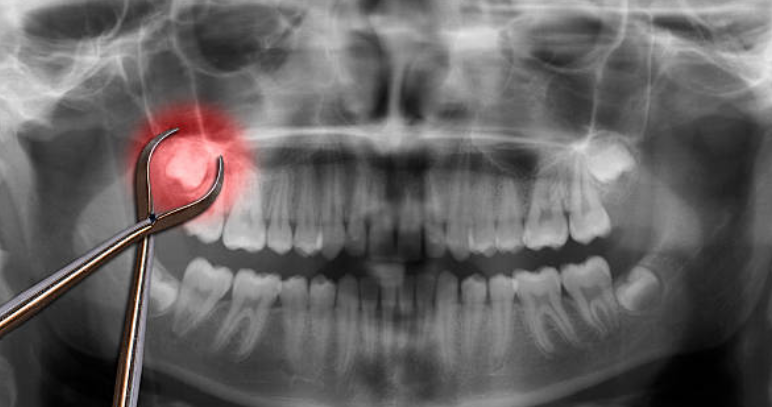

Bleeding after tooth extraction is persistent or excessive bleeding from the socket where a tooth has been removed, typically lasting beyond the normal 24-48 hour healing period. Some bleeding is normal. Light oozing for the first day is expected. However, heavy bleeding that soaks through gauze pads every hour, continues beyond two days, or restarts after initially stopping requires immediate attention from a dental specialist.

This bleeding occurs when the protective blood clot fails to form properly in the empty tooth socket, or when an existing clot becomes dislodged too early in the healing process. The blood clot acts like a natural bandage. Without it, the extraction site remains an open wound. Risk factors include smoking, aggressive rinsing, drinking through straws, or taking certain medications that affect blood clotting. Some patients naturally heal more slowly due to medical conditions or age.